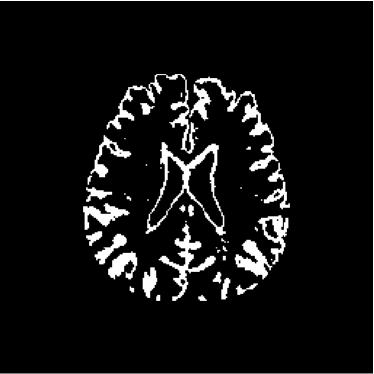

Figure 28 shows 13th slice of classification result obtained by the use of the objective dialectical classifier. Figure 29 exhibits 13th slice of classification result after performing post-labeling, whilst figure 30 shows the entire volume generated by ODC classification.

The training process of ODC algorithm resulted in 6 classes. These classes were reduced to 4 after manual post-labeling, merging 3 classes out of brain region, namely image background, noise and cranial box. The post-labeling is manual because all 3 cited regions are statistically different and, consequently, they are merged due to our interest in classes more related to the brain regions. On figure 29 it is possible to notice that ODC was able to distinguish white matter from the gray matter present in the interface between liquor and white matter.

Figure 29: 13th slice of objective dialectical classification after post-labeling

Refer to caption

Figures 33, 34 and 35 show binary images of 13th slice of ODC classification, showing liquor (cerebrospinal fluid, CSF), gray matter (GM) and white matter (WM), respectively, whilst figures 37 and 38 show the respective morphological spectra and accumulated morphological distributions. Both morphological spectra and accumulated morphological distributions were obtained using structure element square 3×3333\times 3 center (2,2)22(2,2).

Observing figure 34 indicating the detection of gray matter by the objective dialectical classifier, we can perceive the significative reduction of gray matter in brain frontal lobule, better seen in superior part of image. This lobule is directly related with the reduction of recent memory.